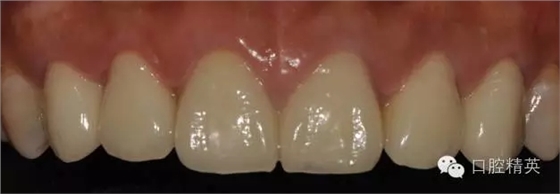

修復(fù)體完成口內(nèi)照片

640.webp (20).jpg